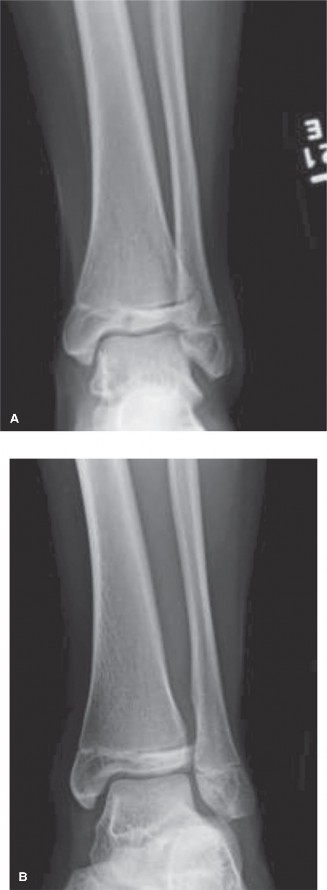

The initial anteroposterior (AP) and lateral radiographs of the right femur demonstrate a complete, displaced, length-stable transverse fracture of the middle third of the femoral diaphysis. There is minimal comminution. The traction splint has effectively restored length, though there remains slight apex-lateral and apex-anterior angulation.

Crucially, dedicated AP and lateral views of the right hip and right knee are obtained. The femoral neck is intact, with no evidence of a basicervical or transcervical fracture—a classic "missed injury" in the setting of high-energy femoral shaft fractures. The distal femoral physis is open and symmetric, with no widening or displacement to suggest a concurrent Salter-Harris injury.

- Radiographs: We expect to see maintenance of alignment and the earliest whispers of periosteal reaction.

At the 6-week follow-up, radiographs typically demonstrate robust, bridging circumferential callus. This is the hallmark of secondary bone healing promoted by the micromotion of the flexible nails.

- Weight Bearing: Once bridging callus is visualized on three out of four cortices (AP and lateral views), the patient is advanced to full weight-bearing as tolerated.